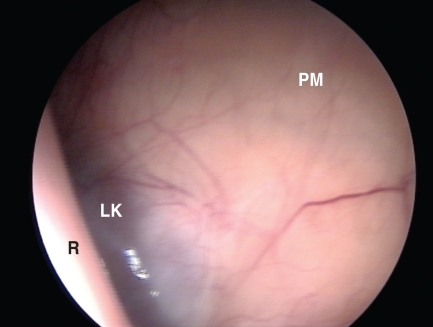

Isobaric left-flank laparoscopy (for access to the left kidney)

The trocar was similarly introduced and directed caudally through the left paralumbar fossa toward the right coxofemoral joint. Once in the peritoneum (as determined by an audible rush of air), the trocar was replaced with the endoscope, which was guided cranially to the upper left quadrant. The dorsal sac of the rumen was gently pushed down with the endoscope, and the left kidney emerged on the screen (Figure 2). The anatomic structures identified were the dorsal sac of the rumen, the left kidney, and the psoas muscle. At the end of the procedure the endoscope was removed and the skin incision closed with a single interrupted suture (2-0 Monosof USS DG nylon polyamide, United States Surgical).

Figure 2.

Isobaric (gasless) laparoscopic view of the left paralumbar approach. R — rumen dorsal sac; LK — left kidney; PM — psoas muscle.